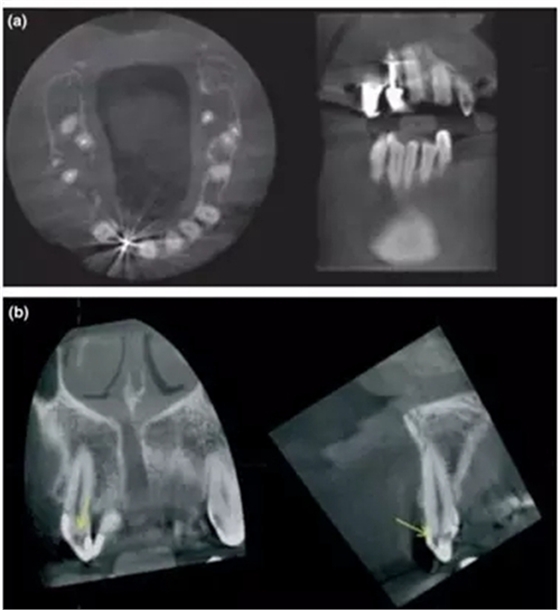

a- 右上2的金屬充填體導(dǎo)致圖像出現(xiàn)散射和射線硬化;

b- 當(dāng)散射影像與牙釉質(zhì)重疊時(shí),容易被誤診為齲齒的透射影 (黃箭頭);

另一個(gè)重要的局限性就是由高密度材料(如金屬樁和全冠)或者鄰近組織(如牙釉質(zhì))所產(chǎn)生的散射和射線硬化,對(duì)CBCT成像質(zhì)量的影響(Mora et al. 2007)。尤其當(dāng)這些影響因素特別靠近檢查區(qū)域時(shí),那CBCT就不能提供足夠的診斷價(jià)值,這時(shí)候臨床醫(yī)生就要考慮其他影像學(xué)檢查手段(Lofthag-Hansen et al. 2007; Estrela et al. 2008)。